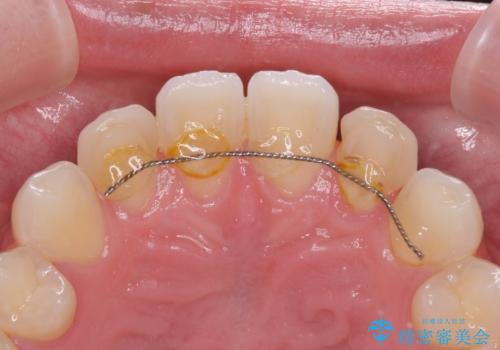

- 前歯のラミネートベニアの不自然な色合いを気にして来院された患者様です。

矯正治療後戻り防止のワイヤー周りにむし歯があったため、オールセラミッククラウンにて補綴することとしました。